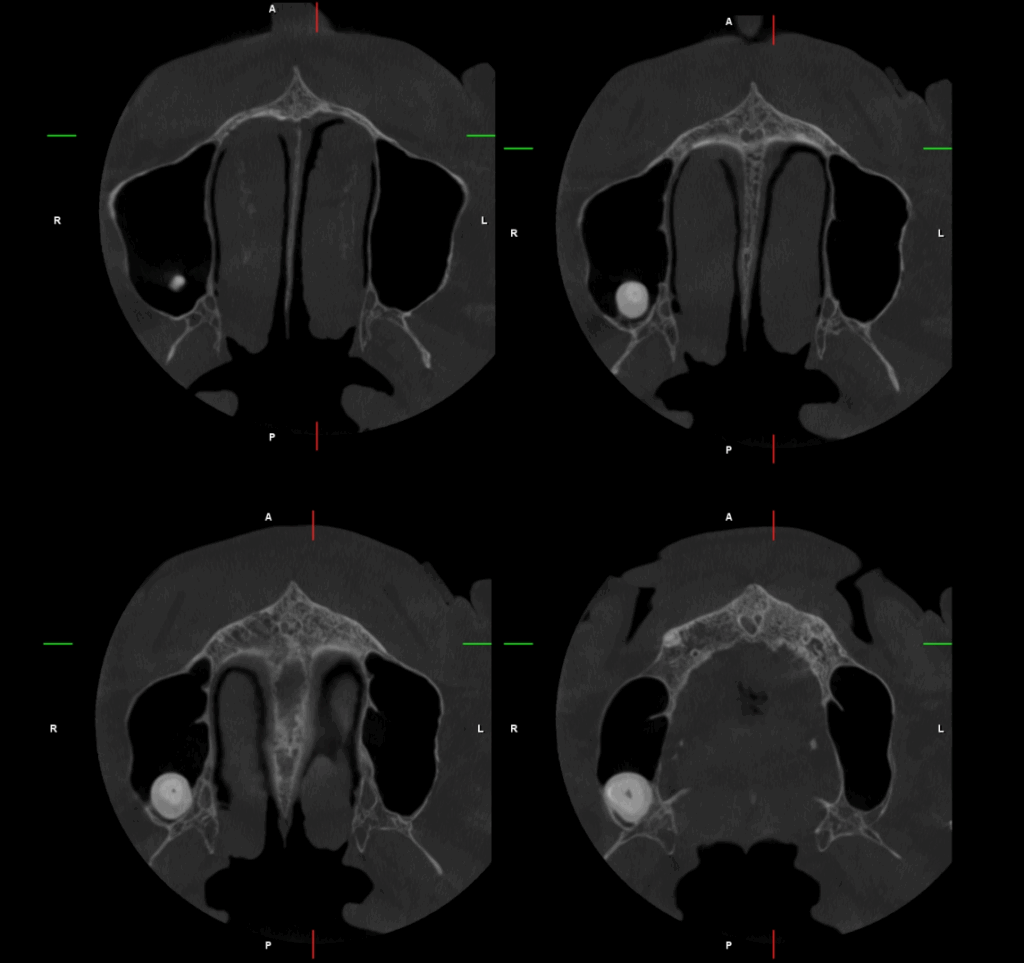

A la evaluación de la tomografía volumétrica (CBCT) en los cortes axiales (Figura 2) y transaxiales (Figura 3), se aprecia pieza 18 orientada hacia vestibular y conducto permeable. Así mismo se evidencia hipercementosis con borramiento del espacio del ligamento periodontal.

CORTES AXIALES